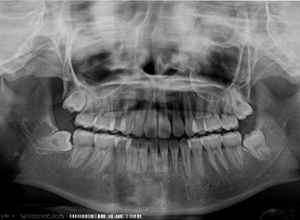

X-Ray所見

セファロ所見 Sellaから下顎頭までの距離は短い。下顎枝、骨体部共に大きく下顎角はそれほど大きくはない。頭蓋底の前後的距離は短くなく、中顔面の奥行きもあるが、NasionからA点までの垂直的距離があるため、下顎はクロックワイズローテーションをしておりⅡ級傾向が認められた。上下顎前歯は唇側傾斜を呈していた。

パノラマ所見 上下顎左右側8は埋伏していた。